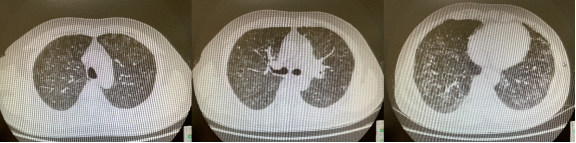

图:HP、煤工尘肺、电焊工尘肺、siderosis、呼吸性细支气管炎

一旦出现了双肺弥漫的腺泡结节,只能提示细支气管炎和肺泡炎,并不能提示是哪种疾病,HP、吸入煤尘、吸入电焊烟尘也可以出现类似表现,因此还需要进一步去分辨到底是暴露了哪种危险因素。[31]